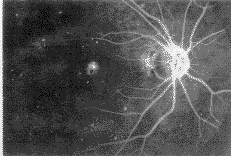

随后因新生血管染料渗漏,荧光素积存在浆液性脱离区,晚期形成边缘模糊的强荧光,见图 5,6.

图5 造影晚期黄斑部新生血管部位边缘模糊的强荧光

图6 造影晚期黄斑部下方边缘模糊的强荧光

在出血部位,造影过程中均呈现荧光遮蔽,表现为与出血范围一致的无荧光暗区.少数病例 可在盘状病变周围出现环形荧光遮蔽,与眼底相应部位对照是黄色脂类渗出物所致,有时在 这种环行渗出物中往往可见新生血管所形成的染料渗漏现象.